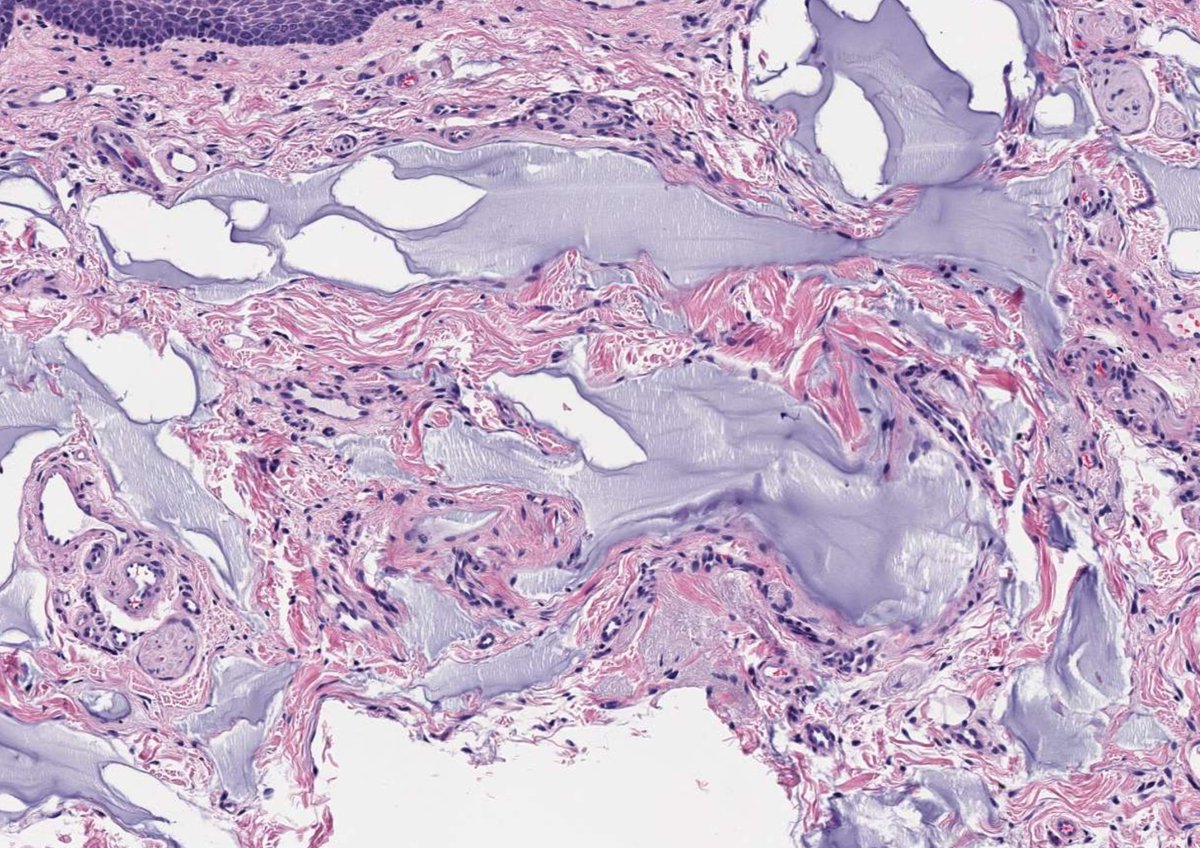

A 59-year-old female with a lip lesion #oralpath #oralpathology #pathology #pathologists #pathTwitter #HeadNeckPathol #HeadandNeckPath #ENTPath #PathologyTweet #dermpath

This is a foreign body consistent with hyaluronic acid filler, showing amorphous basophilic pools of ground substance (Alcian blue/colloidal iron+), typically without foreign body reaction but sometimes with mild fibrosis or secondary inflammation/infection.